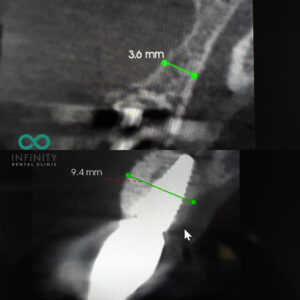

BONE AVAILABILITY?

The amount of bone available in the area where the dental implant needs to be situated is also very important. This information is carefully assessed using a 3-dimensional CBCT scan which enables our team to thoroughly assess the bone volume. In many patients, toothloss often results in bone loss. Likewise, tooth loss may actually have been a result of bone loss. For these reasons, in most patients a bone augmentation (graft) is required alongside treatment to have the dental implant. This will enable us to increase the volume of bone and ensure that the dental implant is positioned in a strong long term foundation of good quality bone.